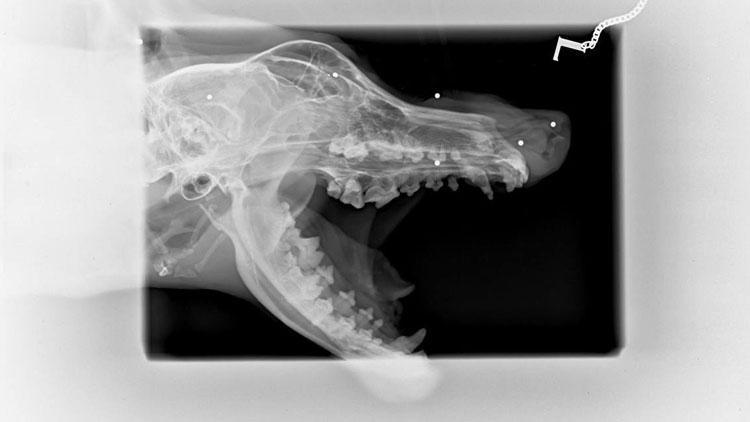

BALIKESİR'in Ayvalık ilçesinde sokaklarda yaşarken, gurbetçi aile tarafından sahiplenilip Almanya'ya götürülen Collie-Terrier cinsi köpeğin, diş bakımı için gittiği veterinerde çekilen röntgeninde, başında 7 saçma tespit edildi. Köpeği sahiplenen Nurferi Bellisan Ortmann, "Bir insanın ne kadar korkak ve sinsi olması gerekir ki; bir masumun yüzüne ateş etsin" dedi.

Ayvalık Belediyesi Hayvan Barınağı'nda bakılırken, birkaç kez yazlıkçılar tarafından sahiplenilen, ancak yeniden terk edilen 'Dük' isimli köpeği, Altınova Mahallesi sokaklarında yaşarken Almanya’da yaşayan Nurferi Bellisan Ortmann ve Jens Ortmann çifti sahiplendi. 20 yıldır ilçedeki yazlıklarında tatillerini geçiren Ortmann çifti, köpeği dönüşte Almanya'ya götürdü. Altınova’dan 2008 yılında sahiplendikleri 'İndra' isimli bir köpekleri daha olan çift, çok sevdikleri Dük’ün dişlerindeki sorun için gittikleri veteriner kliniğinde şoke oldu. Çekilen röntgen filminde, Dük’ün başının çeşitli bölgelerinde 7 saçma olduğu ortaya çıktı.

4 yaşındaki Dük'ün, evlat edinilerek sürekli yeniden sokaklara bırakılma hikayesinin kendisini etkilediğini söyleyen Nurferi Bellisan Ortmann, "Bunlar beni çok etkiledi ve Dük’ü sahiplenmeye karar verdim. Dişleri kötü idi ve tedavi amacıyla röntgen çekildi. Röntgende Dük’ün yüzünde 4 saçma parçası görüldü. Kafatasında toplam 7 saçma saydık. Kontrole gittiğimizde veterinerimizle tekrar konuştuk. Saçma parçalarının isabet ettiği yerler ve çokluğunun önemli olduğunu söyledi. Dük‘ün direk yüzüne ateş edilmiş. Hangi vahşi, hangi amaçla yapmış bilmiyorum. Dük‘ün şimdilik bir sorunu görülmüyor. Saçmalar yumuşak dokuda. Mesela burnunun önündeki, burun çok kanayan bir yapıya sahip olduğu için ameliyatla alınması mümkün değil. Saçmaların zaman içinde yer değiştirmeden zararsız bir şekilde kalmasını diliyoruz. Vücudunun röntgeni çekilmediği için o kısımlarda da var mı bilmiyoruz. Vücuttaki saçma çokluğu ise kurşun zehirlenmesi yaptığından ölümcül oluyor” dedi.

Almanya’da yaşayan ve yine Ayvalık’ta sokakta yaşayan bir köpeği sahiplenen Anke Taner isimli arkadaşının, yürümek istemeyen Boby adını verdiği köpeğinin de omuriliğinde saçma parçalarının olduğunu öğrenince şaşkınlığının arttığını belirten Ortmann, “Aynı gün yine Almanya’da bir arkadaşımın Ayvalık’tan sahiplendiği köpeğin yürümek istemediği için çekilen röntgeninde de omurilikte saçma parçalarının sinirlere baskı yaptığı haberini aldım. Alman arkadaşım şokta idi ve beni aramıştı. Röntgen resimlerini de sosyal medyaya koymak istiyordu. Arkadaşımın köpeği, saçma sinire baskı yaptığı için ve ameliyatla çıkarma işi sinire de zarar vereceğinden her yürüyüşü sancı içinde yapıyormuş. Köpeğine ömür boyu ağrı ilacı vermek zorunda. Türkiye coğrafyası güzel, insanları güzel bir ülkeyken, doğası çöp, insanları da kötü ve güvenilmez oldu. Bir insanın ne kadar korkak ve sinsi olması gerekir ki; bir masumun yüzüne ateş etsin. Utanıyorum artık. Alman veteriner saçmaları gösterirken benim utancımı fark edip 'Her ülkede sapık, cani insanlar vardır' demesi beni teselli etti" diye konuştu.